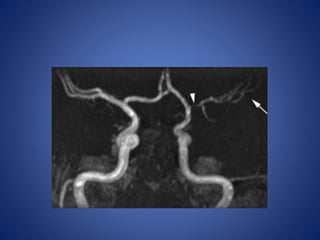

• 7 yr old girl, with sudden onset of severe right sided headache, followed

by left hemiparesis & slurred speech of one day duration.

• H/o Chickenpox 2 months back.

• 7 yrold girl, with sudden onset of severe right sided headache, followed by left hemiparesis & slurred speech of one day duration. • H/o Chickenpox 2 months back.